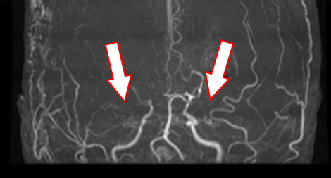

もやもや病のMRA画像

血管造影検査の画像

もやもや病

頭蓋内血管の閉塞がみられます。血管造影では血管が閉塞し、周囲に「もやもや病」がみられます。

バイパス手術によって血管が頭蓋骨を通り、皮膚の太い血管と脳をつなげて治療します。